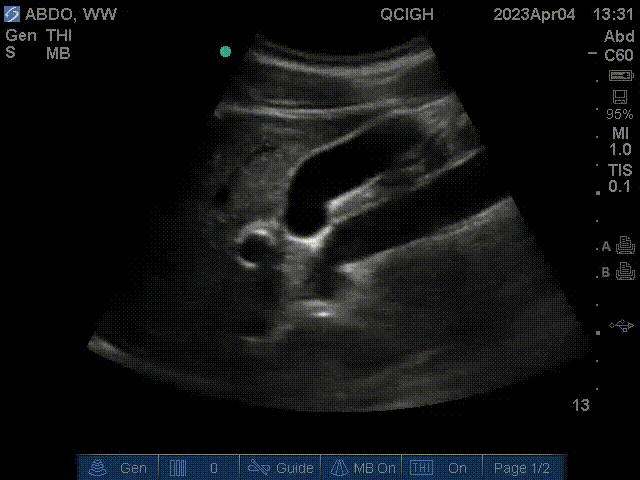

FAST scan – Right kidney

This is a view of the right hepatorenal interface, also known as Morrison’s pouch. The focused assessment with sonography for trauma (FAST) scan aims to identify free fluid in the pericardial space or abdomen. The subxiphoid scan can detect a pericardial effusion. The hepatorenal scan can detect fluid in Morrison’s pouch. The splenorenal scan assesses fluid at the splenorenal interface. The pelvic scan aims to assess for free fluid in the rectouterine or rectovesicular pouch (Douglas pouch). Causes of free fluid in the abdomen include trauma and ascites.